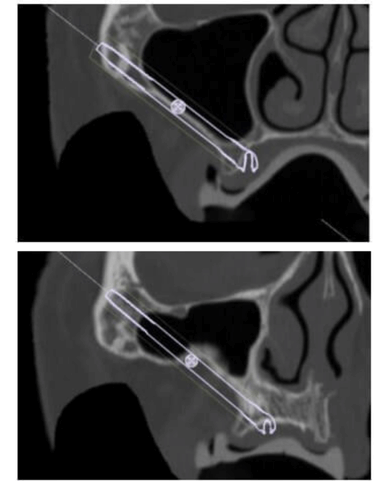

Realizamos CT helicoidal y con FOV ampliado, imprescindible para el diseño de las guías.

Planificamos cuidadosamente la colocación de los implantes teniendo en cuenta, tanto la anatomía maxilofacial como la de la futura prótesis

Planificación 3D y confección de férulas quirúrgicas para abordaje guiado.

Se colocan 4 implantes Zygoma según planificación 3D guiada bajo sedación IV, Carga inmediata a las 24 horas.